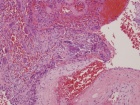

16 yo male with complaints of worsening, mild pelvic pain, increased with rotation of his right hip. He denies constitutional symptoms or history of trauma.

PE: Healthy appearing adolescent male. Normal stance and gait. RLE: Pain with IR and ER of hip. NVI w/o LAN

Zoom image: Cell stain Cell stain.